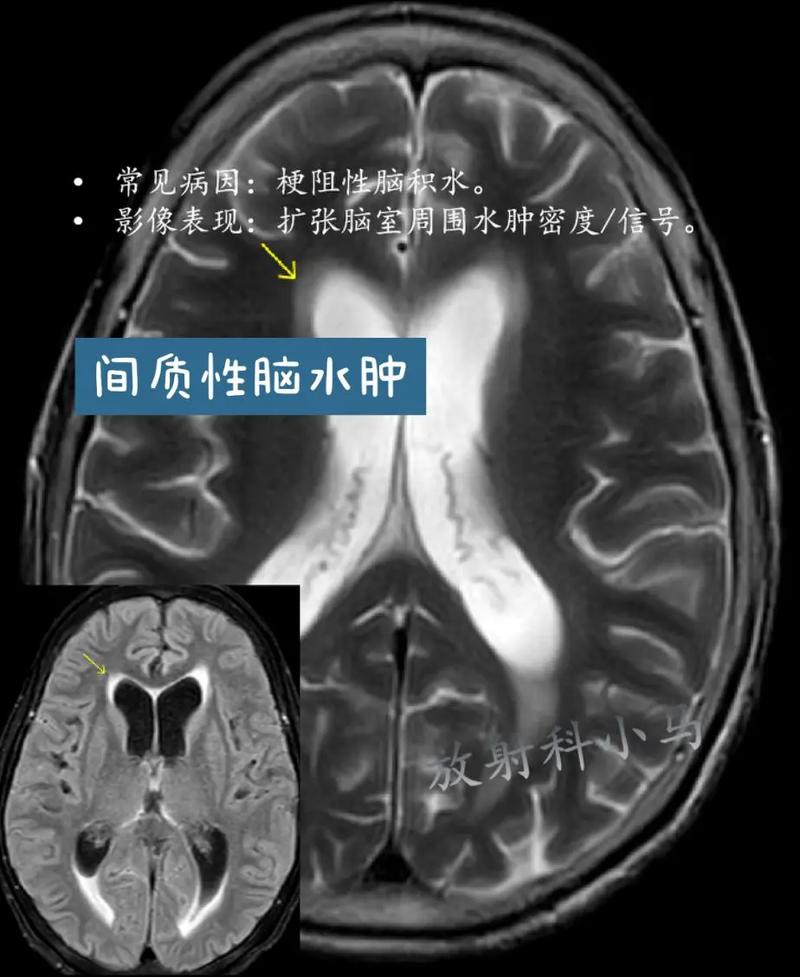

脑梗死后水肿主要分为两个阶段,它们相互关联,共同对大脑造成损害。

血管源性水肿

这是在细胞毒性水肿的基础上发展而来的,通常发生在脑梗死后数小时到数天。

- 梗死核心区的缺氧和炎症反应会破坏构成血脑屏障的脑血管内皮细胞。

- 血脑屏障就像一个“安检门”,严格控制着血液中的物质进入大脑,当它被破坏后,这个“安检门”就失效了。

- 血液中富含蛋白质的液体就会从血管内漏出到细胞外的间隙中,导致细胞外间隙显著扩大。

- 主要影响的是细胞外间隙。

- 这会导致脑组织整体性、弥漫性肿胀,颅内压力急剧升高。